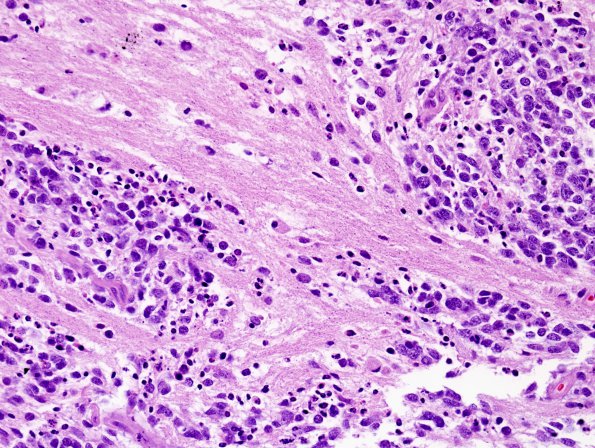

ETMR - Embryonal Tumor Multilayered Rosettes

In some tumor regions primitive cells, neurocytes and neuropil are admixed (H&E)